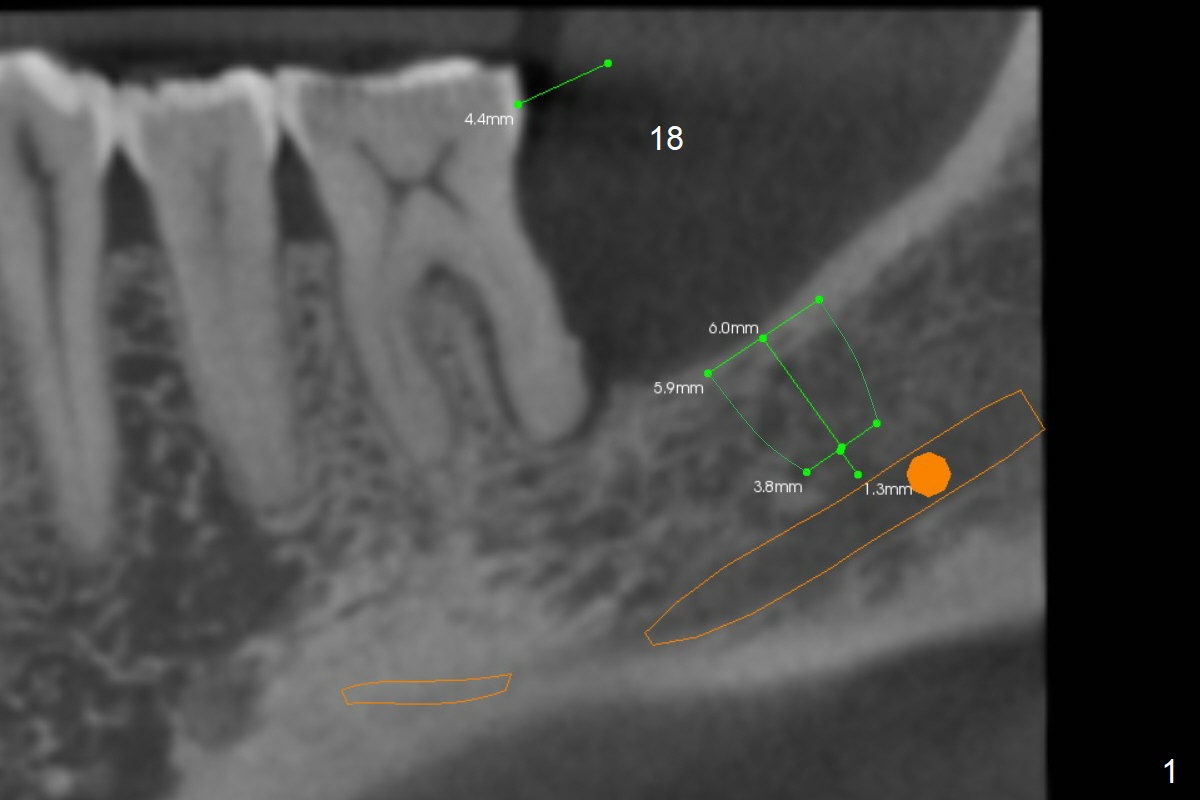

A 57-year-old man has severe bone loss at #18 (Fig.1). It appears that there are 3 sites of placement of an implant (Fig.2,3).